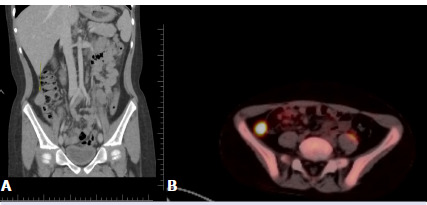

Xanthogranulomatous inflammation is a rare chronic inflammatory reaction. Appendiceal involvement in the pediatric age group is extremely rare. We present a case of xanthogranulomatous appendicitis (XGA) that was detected incidentally during the excision of a residual intraabdominal mass in an 8-year-old male patient who was treated for Burkitt lymphoma. An 8-year-old male patient who had been diagnosed with Burkitt lymphoma underwent abdominal computerized tomography for evaluation after chemotherapy. An approximately 2.5 cm mass in the right lower quadrant of the abdomen was detected, and laparoscopic excision of the mass was planned. During the operation, it was noticed that the appendix (adjacent to the mass) was golden yellow in color and abnormal in appearance, so a synchronous appendectomy was performed. The pathology result of the mass was compatible with Burkitt lymphoma. Microscopic examination of the appendix revealed that the columnar surface epithelium had eroded and been replaced by fibrin and cell debris. Inflammatory cell infiltration rich in foamy histiocytes as well as lymphocytes and sparse neutrophils that form destructive aggregates was observed in all appendiceal layers. The final diagnosis of the appendectomy specimen was compatible with XGA. In very few XGA cases, the appendix is described as bright yellow or golden yellow. The diagnosis is usually made by the pathological examination after surgery. Though the diagnosis was made postoperatively in our case, there is now, for the first time in the literature, a view of the golden yellow color of XGA taken from an intraoperative video clip.